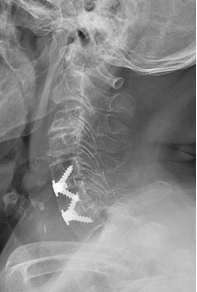

图2 患者术后颈椎X片

7月2日,在多学科精心准备下,刘浩教授采用零切迹假体内固定技术为该患者实施了双节段颈椎前路椎间融合术。凭借丰富成熟的经验,手术耗时1小时10分钟,术中出血量约10ml,患者未安置尿管及引流管。手术当天下午,患者佩戴颈托下床活动,左上肢疼痛麻木症状明显改善,晚上正常进食。7月4日,患者转入全科医学病房继续后续康复治疗,一周后,患者顺利出院。目前,患者左上肢无明显疼痛麻木,生活质量较术前明显改善。